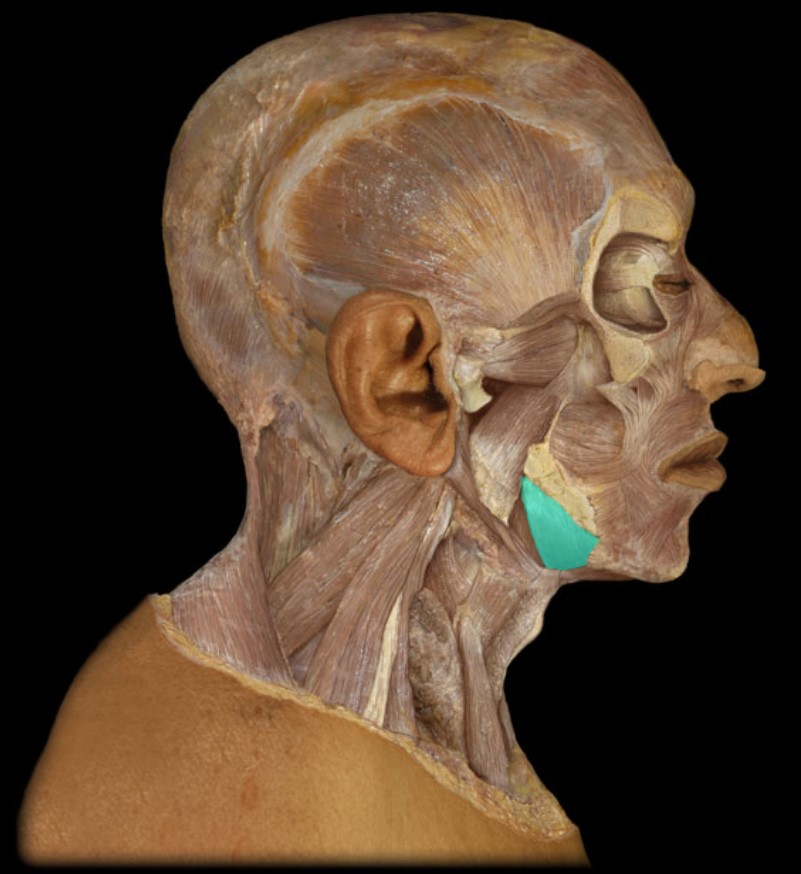

Thyroid Gland

Mandible

Mylohyoid

Geniohyoid

Hyoid